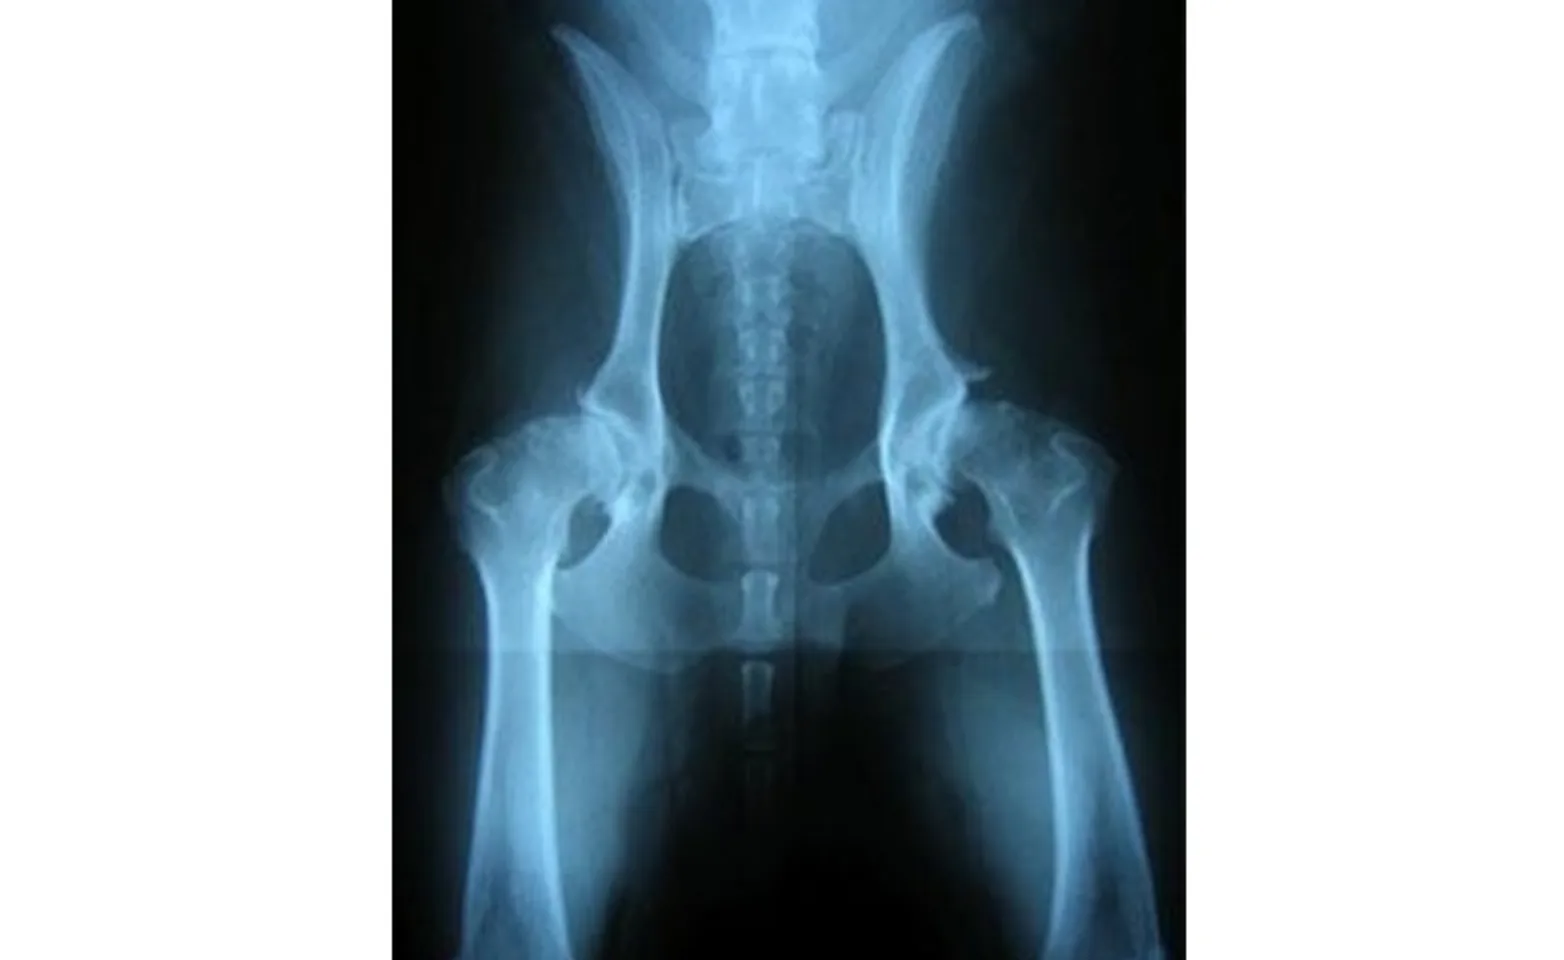

In older dogs, there is often severe flattening of the femoral head, a shallow acetabulum, and signs of arthritis: abnormal bone formation, osteophytes (bone spurs), and collapse of the joint space (Figure 4).

Figure 4: Radiograph of canine hips with severe osteoarthritis seen with the chronic adult form of hip dysplasia.